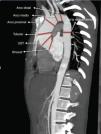

El PFC fue categorizado siguiendo la clasificación de Sievers (2007)5: a) tipo 0 (VAB pura, sin rafe); b) tipo 1 (morfología valvular más frecuente con un rafe entre los 2 velos), que se subdivide en: tipo 1 con fusión de velo aórtico izquierdo-derecho (tipo 1 I-D, el más frecuente), tipo 1 con fusión de velo derecho-velo no coronariano (tipo 1 D-NC, el segundo más frecuente), tipo 1 con fusión de velo izquierdo-no coronariano (tipo 1 I-NC, muy infrecuente), y por último, c) tipo 2 (con 2 rafes, monocúspide) (fig. 1).

Con la tomografía de tórax preoperatoria realizamos mediciones de la aorta ascendente a varios niveles: sinusal, unión sino-tubular (UST), tubular, arco proximal (AP), arco medio (AM), arco distal (AD) y aorta torácica descendente (fig. 2).